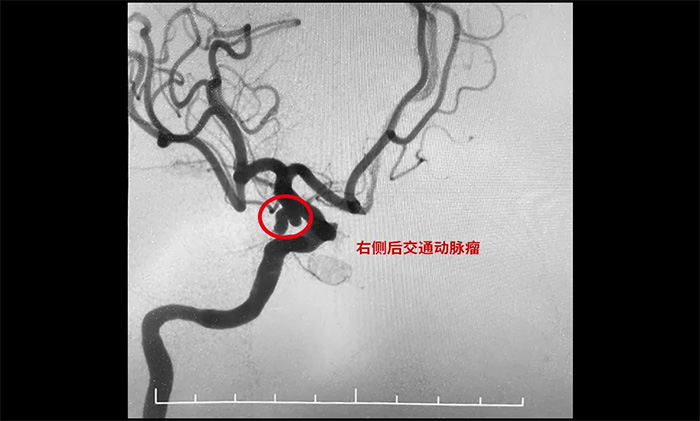

《长江日报》2023年10月18日报道,55岁的张女士参加家庭聚会唱《青藏高原》飙高音时,突然头疼剧烈、恶心呕吐,家人紧急将其送医。医院给她做了全脑血管造影,最后发现是动脉瘤破裂。

▲ 栓塞前

▲ 栓塞后